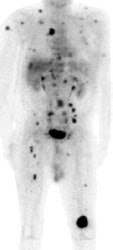

Widespread melanoma metastatses- The case below is from a 53 year old male with metastatic melanoma. The exam demonstrates multiple soft tissue, lung, and osseous metastases. Note the larger field of imaging for the evaluation of metastatic melanoma which extends to below the knees. Some centers will perform whole body examinations in patients with melanoma. Note the faint gonadal activity and the markedly amount of activity within the distended urinary bladder. The exam was performed on an ECAT EXACT PET scanner (CTI) using a dose of 10.2 mCi FDG. Case courtesy of Oregon Positron Imaging, LLC, Albany, Oregon and CTI (The power behind PET). Click image to view cine avi file (230K) |